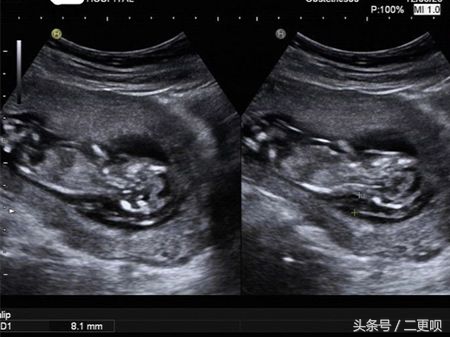

还好一切都正常 漫长的孕程我走了三分之一拉。附上NT B超图

NT是(nuchal translucecy, NT),是胎儿颈部半透明膜的缩写,是胎儿的第一次畸形排查。它的厚度与胎儿DS缺陷正相关,并可以通过超声成像测量。用于评估胎儿是否会患唐氏婴儿的一种。所以还在问到底要不要去做NT的准妈妈,不要再犹豫拉。为了宝宝健康!

准妈妈最好在孕11-14周内做NT最好,因为11周前由于胎儿太小,无法观察颈后透明带,而14周的过后胎儿会逐渐发育,可能会将颈项透明层出多余的体液吸收,影响检测结果。所以建议准妈妈在11-14周内去做NT。